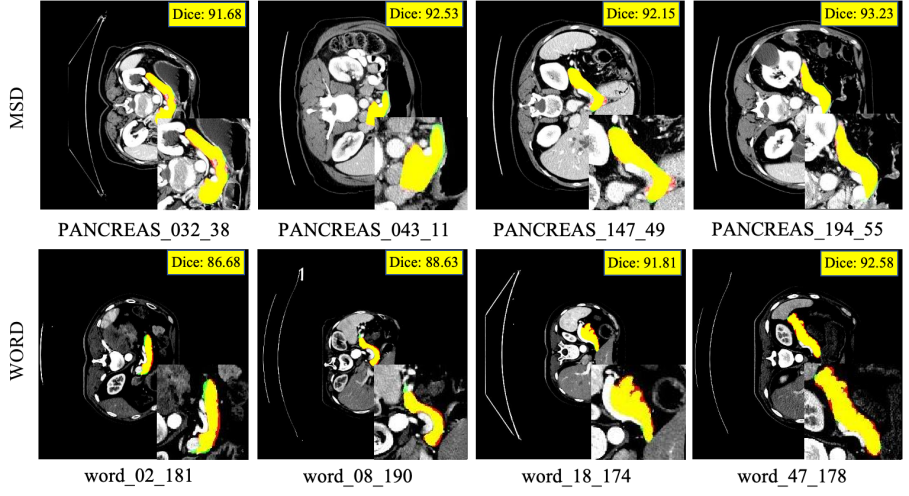

Refer to caption

Figure 3: Segmentation results on the MSD dataset (first row) and the WORD dataset (second row). Contours: Red = Gold Standard, Green = Predicted Result.

Similar results could also be obtained on other datasets, and the proposed model demonstrated accurate and robust performance. Compared with the existing state-of-the-art methods shown in TABlE 3, the mean and variance of the proposed method are very stable. The proposed model achieved the optimal results on the main evaluation metric Dice, and the optimal and suboptimal results on the Jaccard metric. While maintaining the coverage rate, the other two auxiliary indicators also demonstrated excellent performance. As shown in Fig.2 and Fig.3, most of our segmentation results overlap with the gold standard on four datasets.